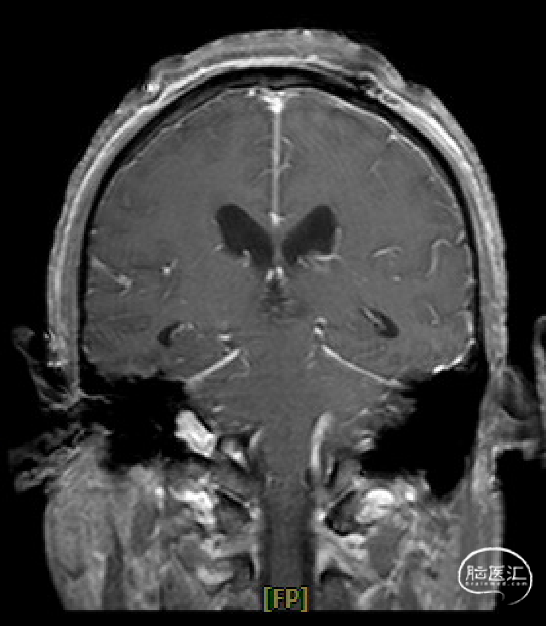

术前MRI与术后复查MRI对比

术区无出血,脑室系统较术前显著缩小,脑积水缓解。

术后1天复查CT